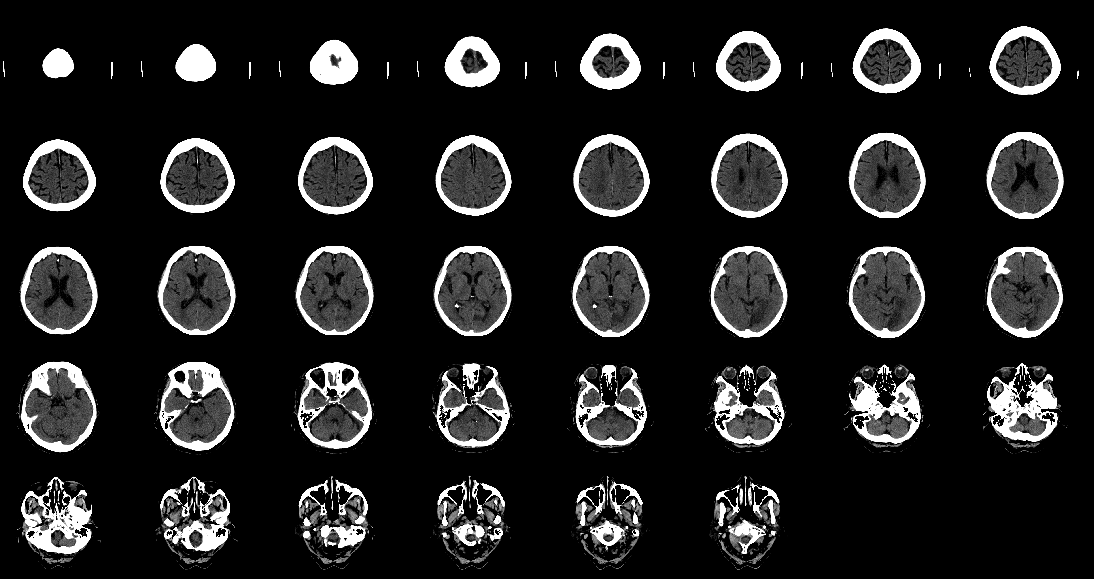

Figure 15: Fictional image of a BCT generated with the flow-based generative model.

Finally, a fictional image generated for BCTs is shown in Fig. 15.